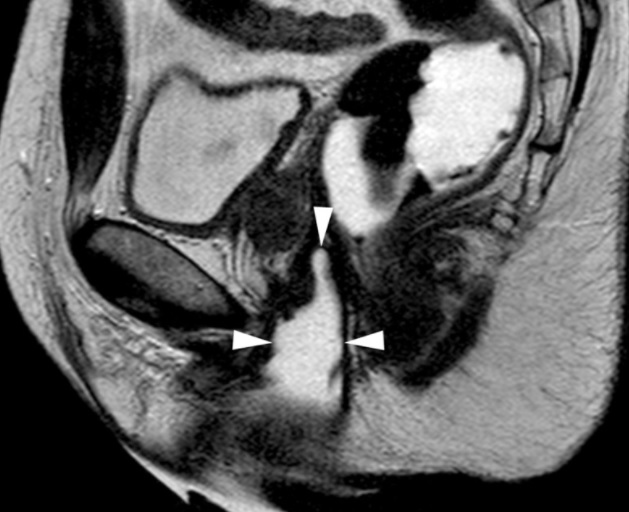

this is a view from the side of a patient. their spine is on the right hand side. the arrows show the border of the neovaginal canal. Just imagine the type of shit that builds up in the top of this shape.